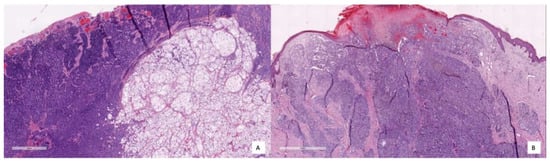

To better illustrate how the model diagnoses, different pictures of the cases corresponding respectively to TNs, TPs and FPs are shown in Figure 8, Figure 9 and Figure 10. Figure 8 shows several examples of TN cases, including a case of dermal melanocytic nevus (Figure 8A), a Reed nevus (Figure 8B), a Spitz nevus (Figure 8C) and a dysplastic nevus (Figure 8D). Figure 9 shows two examples of True Positive (TP) cases, including a spreading superficial melanoma of 3.79mm of Breslow thickness with balloon degeneration (case A) and a superficial spreading melanoma, ulcerated of 5.5 mm of Breslow thickness (case B).

As said earlier, only two cases were classified as FP with the KNN model and only one with the RF model. Coincidentally, both models failed to classify the same case (a deep blue nevus) as benign. The histopathological features of the two FP cases are compiled in Table 5, and the images are shown in Figure 10. In Case A, the deep infiltration of the pigmented melanocytes and the spindled shape may be misinterpreted; in Case B, there is a basal proliferation of pigmented melanocytes.